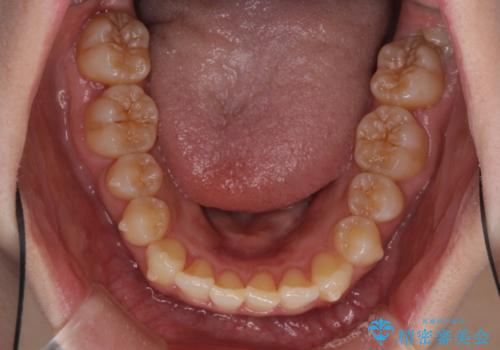

- 前歯のデコボコと奥歯の不正咬合を気にして来院された患者様です。

左右の大臼歯が全て鋏状咬合(シザーズバイト)になっており、治療が難航することが予想されましたが、インビザラインにより治療を行うこととしました。

最難関と思われたシザーズバイトは比較的短期間で解消されました。

しかし、治療中に2度の出産を経験され、治療期間は長くなってしまいましたが、咬みやすく、清掃しやすい歯列を獲得することができました。